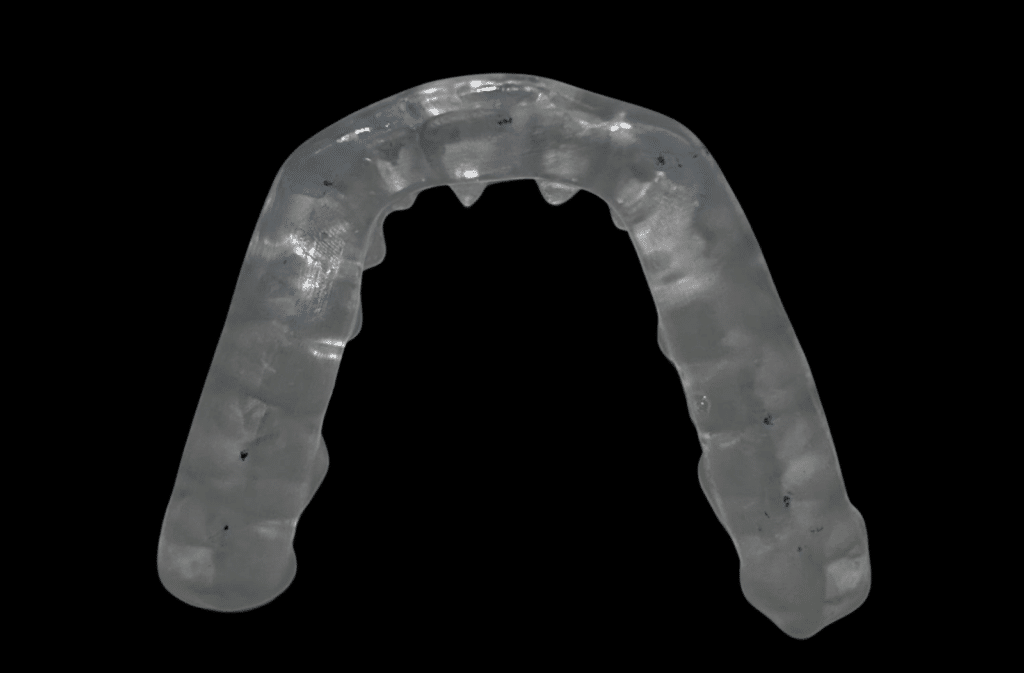

TMJ Splint Treatment

drosmanakinciTMJ Splint Treatment in Türkiye: Get the most affordable TMJ splint in 1 day! Temporomandibular…

TMJ Orthotic Treatment

drosmanakinciTMJ Orthotic Treatment in Turkey: Relieve Pain and Restore Harmony Temporomandibular Joint (TMJ) disorders can…